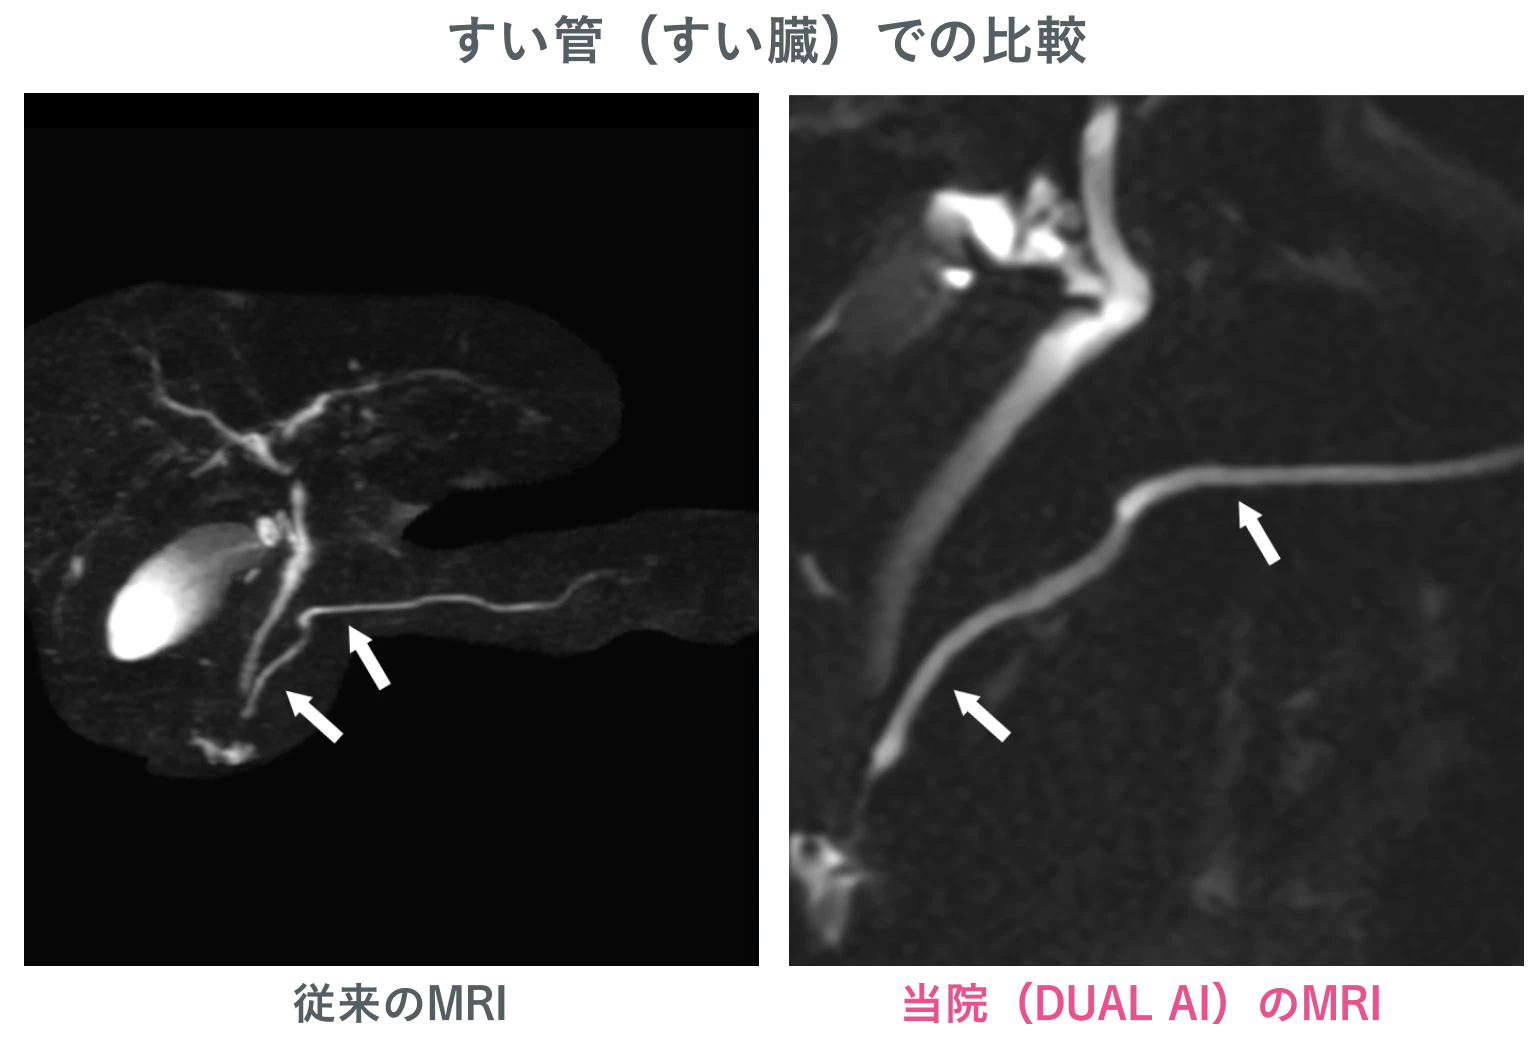

高原クリニック イノベーティブスキャンのMRIは、すい臓がんの早期発見において高精度な診断を実現しています。